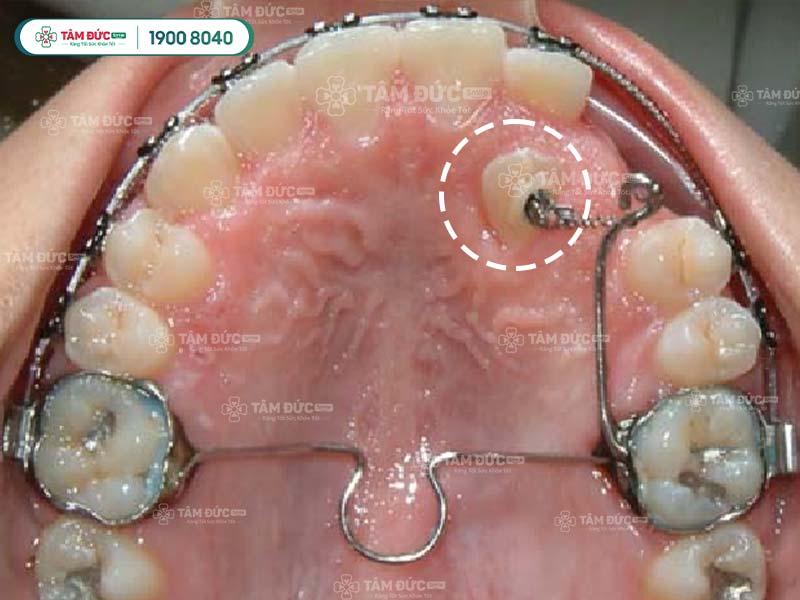

5.2. Giai đoạn 2: Phẫu thuật bộc lộ răng

Nếu răng ngầm nằm sâu trong xương hàm, bác sĩ cần thực hiện phẫu thuật bộc lộ răng để lộ phần thân răng ra ngoài. Phẫu thuật này được thực hiện dưới gây tê tại chỗ, nên sẽ không cảm thấy đau đớn.

5.3. Giai đoạn 3: Kéo răng

Sau khi răng đã được bộc lộ, bác sĩ sẽ sử dụng hệ thống lực kéo để di chuyển răng lên trên cung hàm. Có 3 loại hệ thống lực kéo chính:

- Neo giữ tại răng: Sử dụng dây cung hoặc thun buộc để neo vào các răng liền kề.

- Neo giữ tại xương: Sử dụng vít cấy ghép vào xương hàm để neo lực kéo.

- Neo giữ hỗn hợp: Sử dụng cả neo giữ tại răng và neo giữ tại xương.